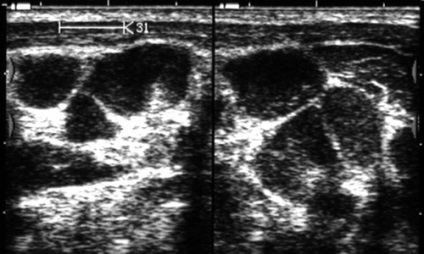

Ábra. 39. nyirokcsomók a nyakon limfoproliferatív betegség (szövettanilag: lymphosarcoma).